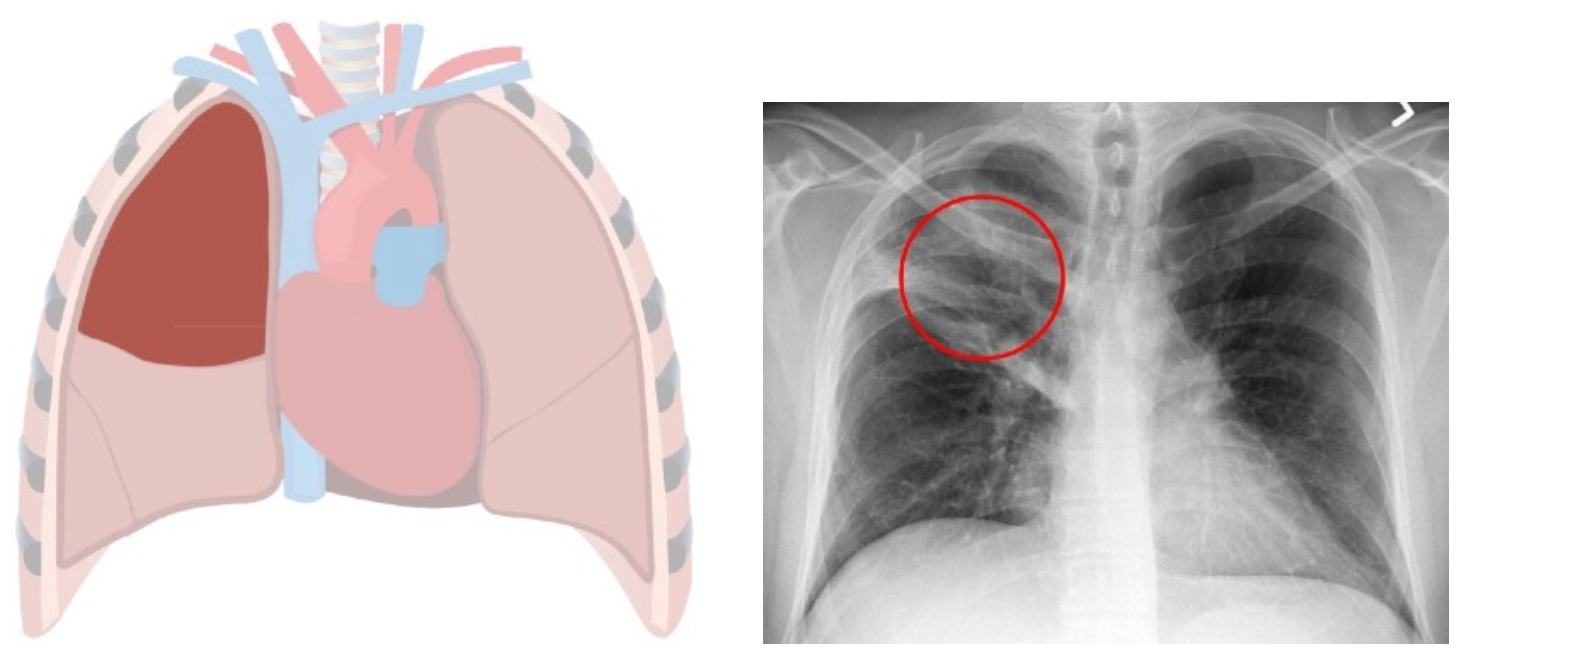

Chest x-ray helps to diagnose lobar pneumonia. The x-ray will show the pus and other substances in the affected lung lobe, which has a cloudy white appearance on the x- ray. Here are some examples of chest x-rays showing infection in different lobes: